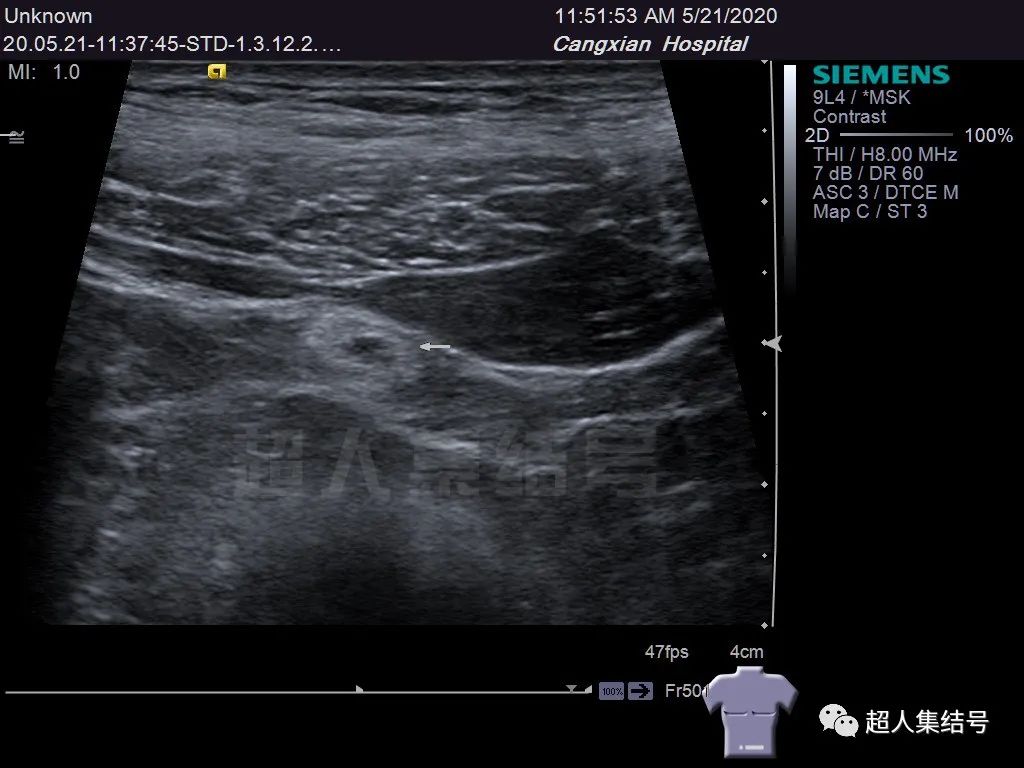

脐尿管憩室并结石 超人集结号 微信公众号文章阅读 Wemp